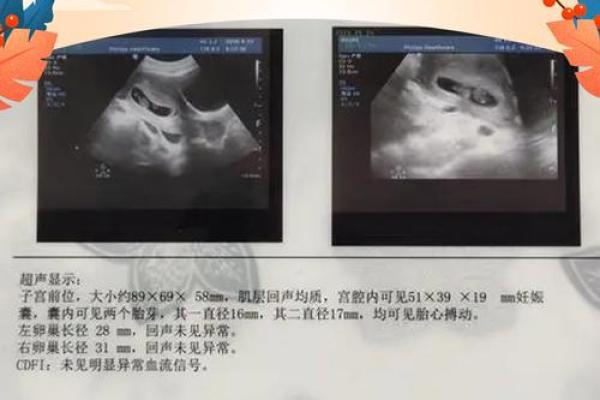

7、看孕 *** 胎位。胎位靠下的怀的是男孩,反之考上的会生女孩。靠近腹部右边的话怀男孩,靠近腹部左边的怀的是女孩。

9、从宝宝胎心来看。如果怀孕时胎心较慢(每分钟低于140以下),怀男孩可能性更大。反之胎心较快,怀女孩可能性大。